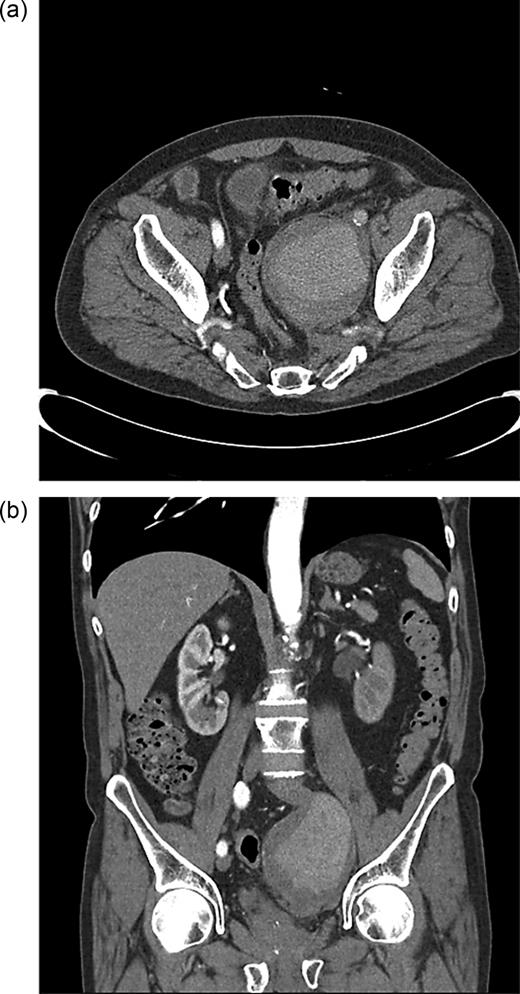

Computed tomography (CT) angiography was requested, and the patient was started on antibiotics because of the concerns over a mycotic aneurysm after discussion with the vascular team. CT angiography showed the internal iliac aneurysm obstructing the left ureter and abutting local nerve roots, with atheromatous disease within the common femoral arteries with an ectatic aorta (Figure 2a and b).